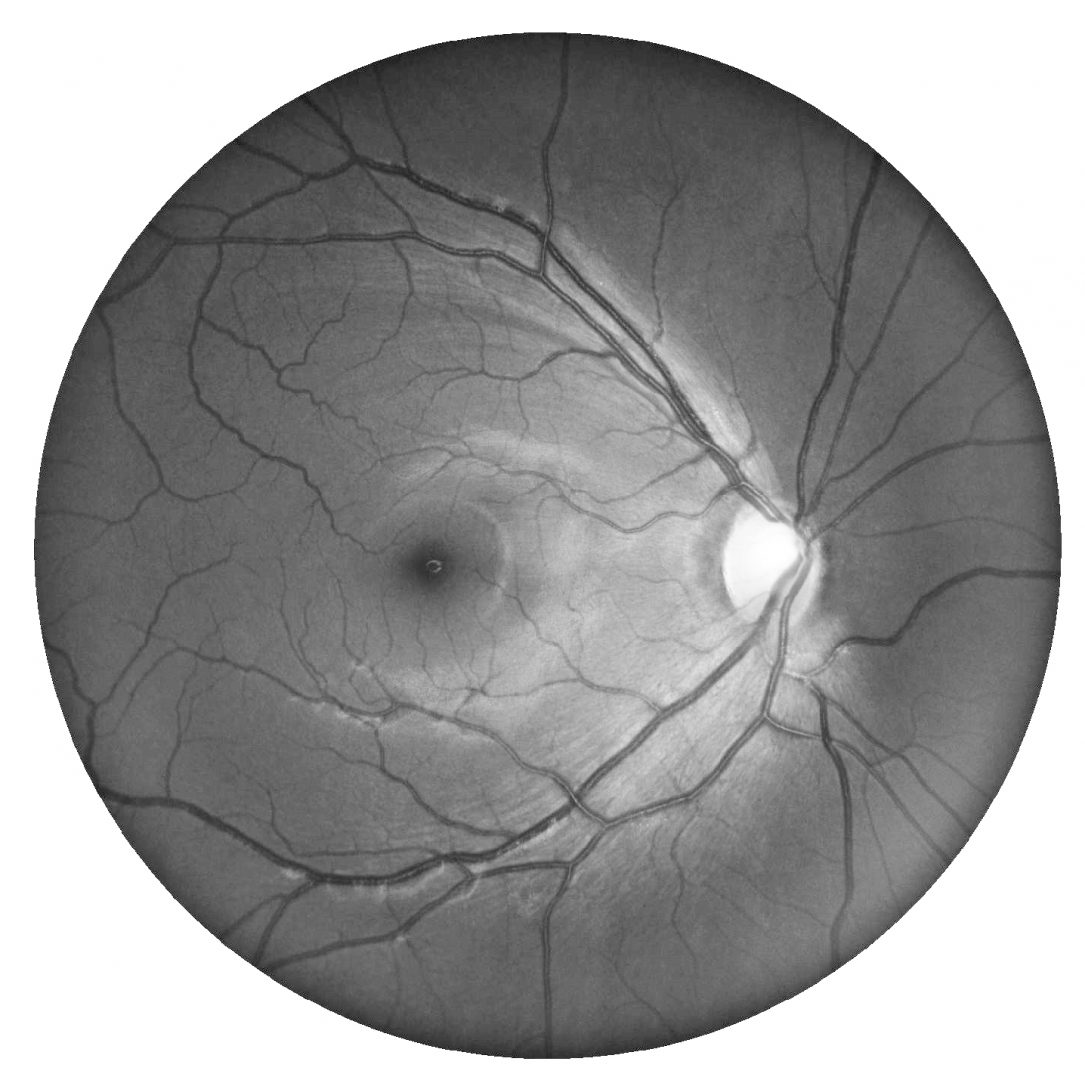

Funduscopically, a thinning of the RNFL and associated loss of the normal reflectivity is noted superiorly. Superior peripapillary atrophy and disc pallor with dense inferior altitudinal field defects are typically noted. Additionally, the superior branch of the central retinal artery enters the eye in a more superior location than is typical.

Retinal photo and red-free image (right and left eye)